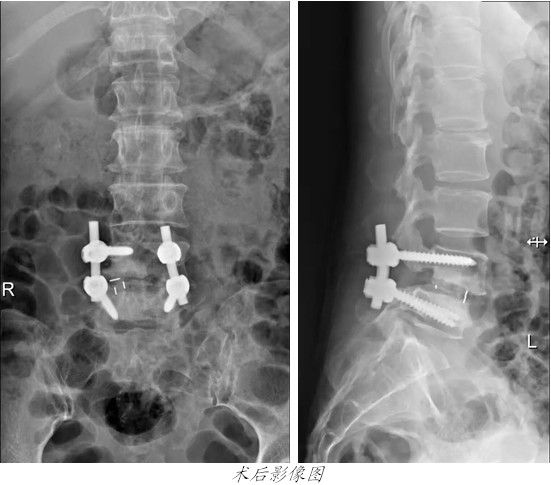

• 康美醫院開展微創手術治療腰椎滑脫 康美醫院開展微創手術治療腰椎滑脫2016-10-25

昨天,康美醫院爲一名腰椎滑脫患者成功進行了脊柱微創手術。

患者歐**,女,48歲,兩個多月前無明顯誘因出現腰部疼痛伴右大腿酸痛,予以康複理療及口服藥物治療,症狀稍減輕,但反複出現。來我院行腰椎MRI檢查,結果顯示第四腰椎向前滑脫,雙側椎弓峽不連,随入住我院外四科(骨科)。

經外四科主任吳志斌詳細檢查,認爲患者第四腰椎真性滑脫,Meyerding分級爲Ⅱ度,腰4/5椎間隙消失,神經壓迫症狀明顯,一般治療難以改善患者日常生活質量,有手術治療指征。經與患者溝通一緻,昨天[ 查看詳細 ]